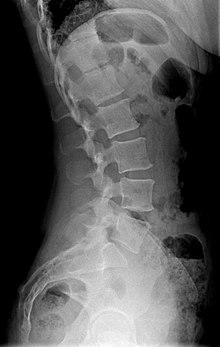

X-ray of lumbar hyperlordosis

Measurement and diagnosis of lumbar hyperlordosis can be difficult. Obliteration of vertebral end-plate landmarks by interbody fusion may make the traditional measurement of segmental lumbar lordosis more difficult. Because the L4–L5 and L5–S1 levels are most commonly involved in fusion procedures, or arthrodesis, and contribute to normal lumbar lordosis, it is helpful to identify a reproducible and accurate means of measuring segmental lordosis at these levels.[16][17] A visible sign of hyperlordosis is an abnormally large arch of the lower back and the person appears to be puffing out his or her stomach and buttocks.

Precise diagnosis is done by looking at a complete medical history, physical examination and other tests of the patient. X-rays are used to measure the lumbar curvature. On a lateral X-ray, a normal range of the lordotic curvature of between 20° and 60° has been proposed by Stagnara et al., as measured from the inferior endplate of Th12 to the inferior endplate of L5.[18] The Scoliosis Research Society has proposed a range of 40° and 60° as measured between the upper endplate of Th12 and the upper endplate of S1.[18] Individual studies, although using other reference points, have found normal ranges up to approximately 85°.[18] It is generally more pronounced in females.[18] It is relatively constant through adolescence and young adulthood, but decreases in the elderly.[18]